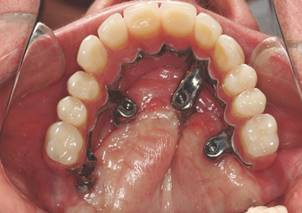

Attempts of changing protocol, through the buccal approaches, change in implant design, change of incline of implant head or use new intermediates, aim to optimize the rehabilitation, both phonetically as in the biomechanics of the system.1-3 Maxillae with large buccal concavity and transversal atresia restrict the results obtained in this techniques. In favorable situations, with enough bone, these technical changes offer little benefit compared to the original protocol, because both are performed in situations of good prognosis. In cases of facial deformities and big atresias, the buccal approaches are interesting, since it does not exist the possibility of alveolar anchoring.4 This are borderline cases, where there is not the best option to treatment, even considering the risks. In the conventional cases, the alveolar anchoring is very important and must be considered (Figs. 5 and 6).